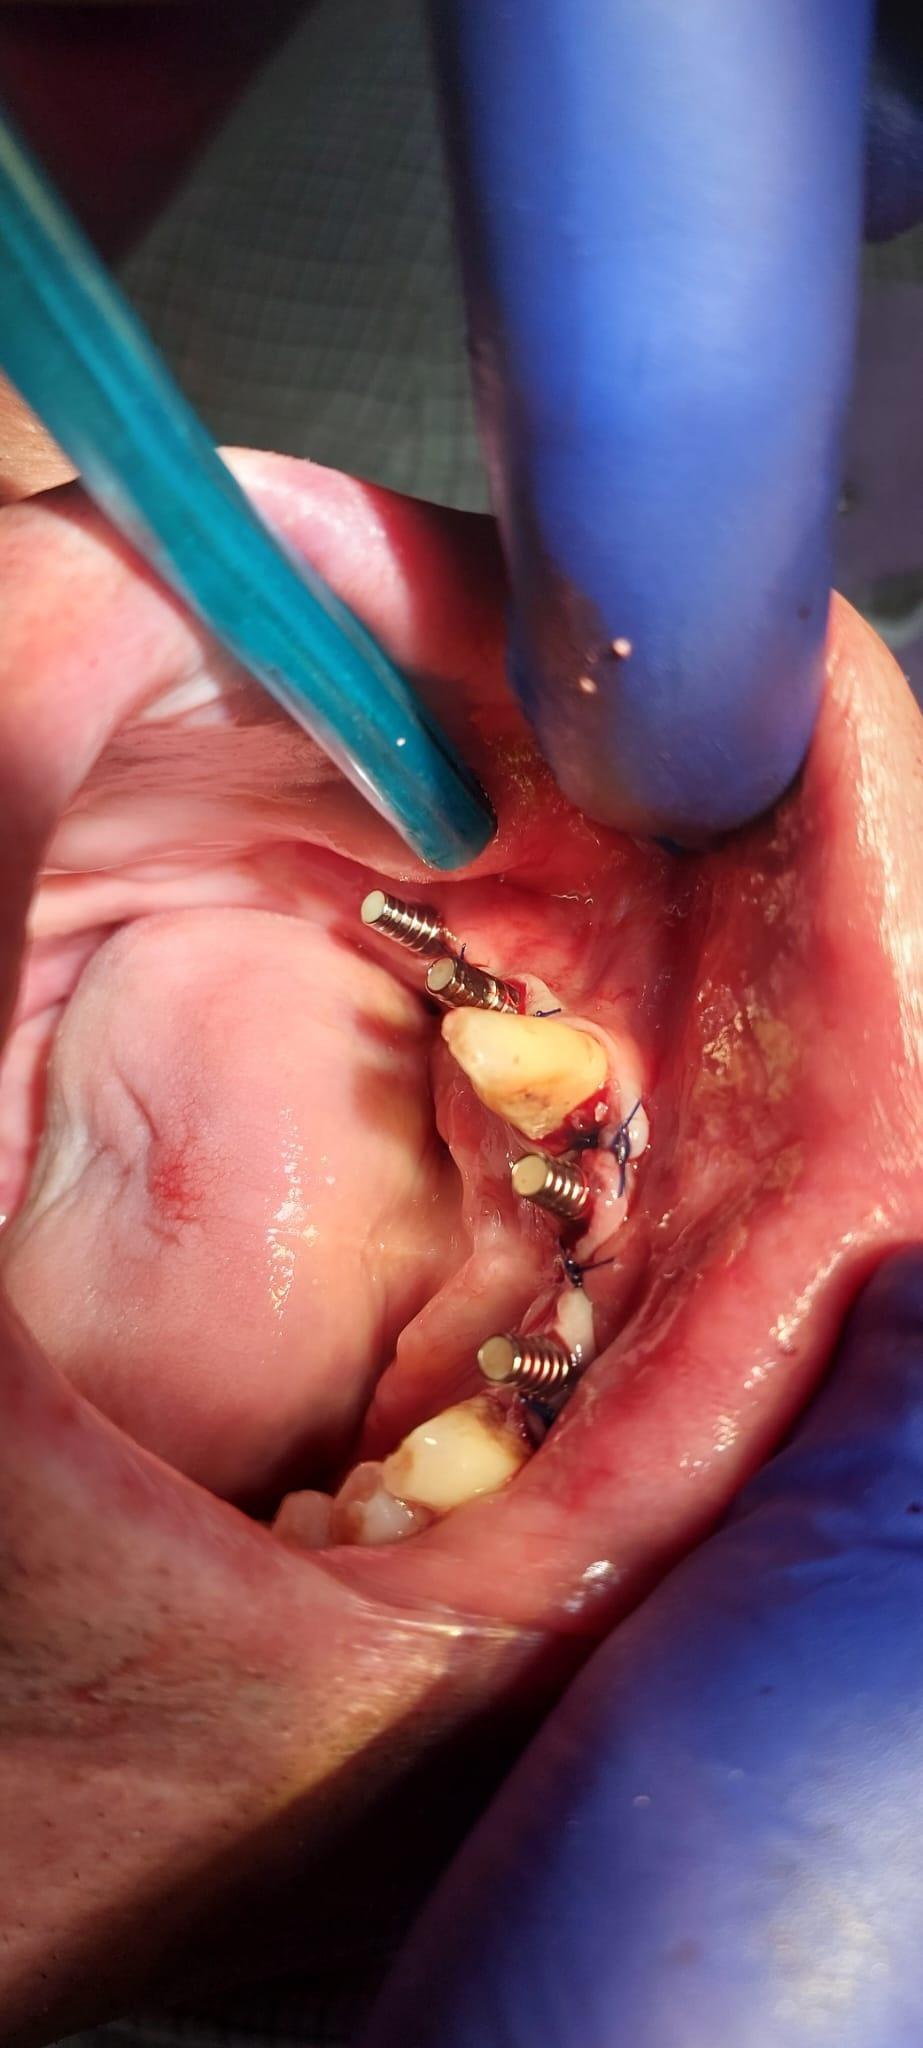

IMPLANTOLOGIE

SUPRAPROTEZAREA PE IMPLANT